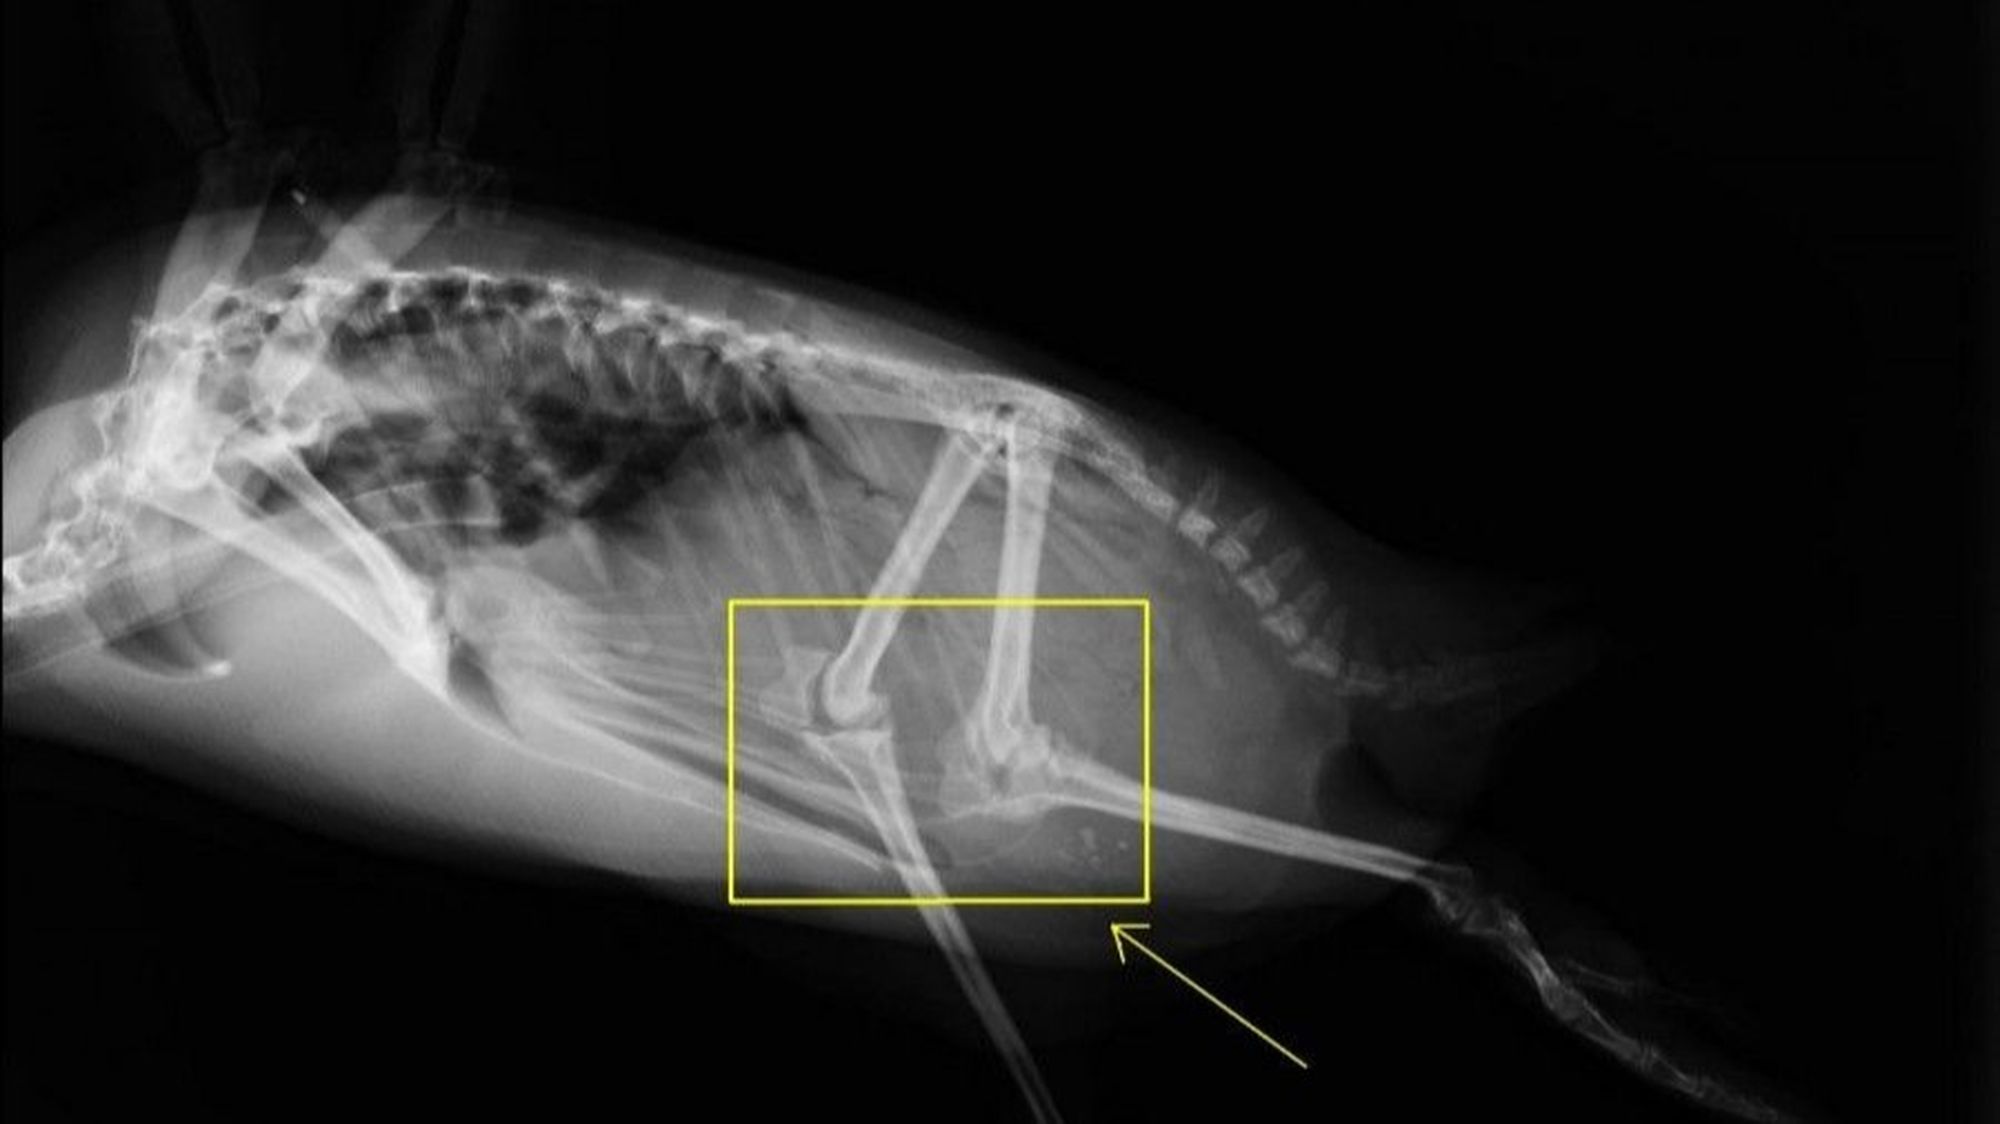

Elbette hayır. Fotoğrafta gördüğünüz bir penguenin X-Işını Taraması altındaki bacak kemiklerinin görüntüsü.

Penguenlerin dizleri, vücutlarının içerisinde yer alır; dışarıdan gözükmez. Ancak dikkatli bir inceleme, evrimsel öngörünün tam da ileri sürdüğünün penguenler için de geçerli olduğunu ortaya çıkaracaktır: Penguenler de, diğer tüm omurgalılarla aynı vücut planını paylaşmaktadır.